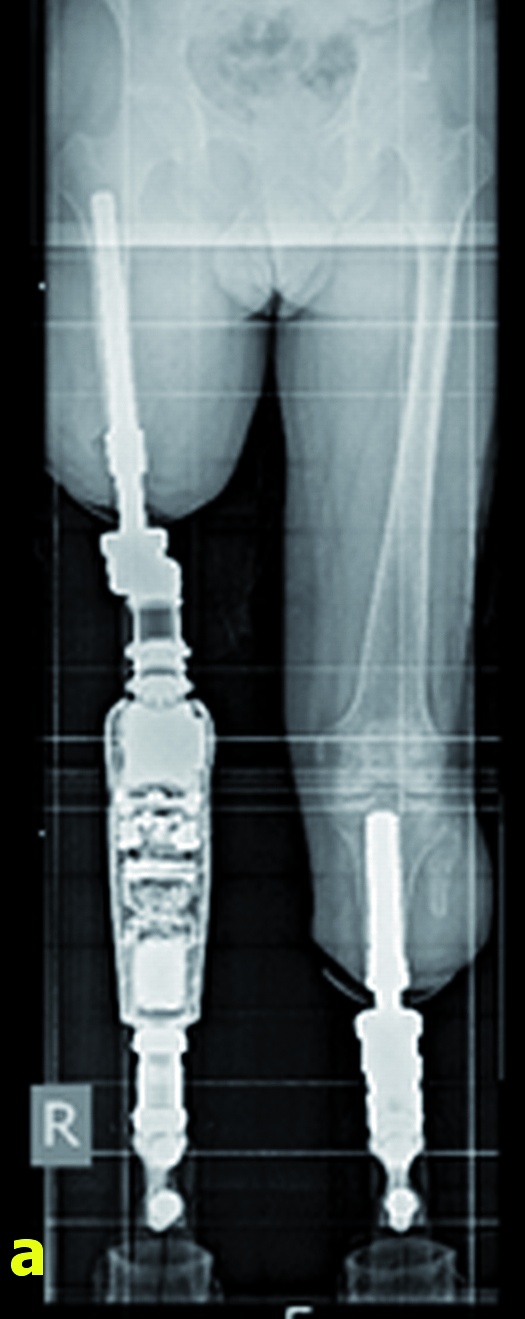

Nach individueller Fertigung der Implantate erfolgte im April 2016 in einem ersten Operationsschritt die Implantation der sogenannten „Endomodule“ in den rechten Femur- sowie den linken Tibiastumpf. Der Femurstumpf wurde dabei unter Entfernung der dehiszenten Knochenlamelle um 5,5 cm gekürzt. Der postoperative Verlauf wurde durch eine Pneumonie und eine passagere Blutungsanämie erschwert; wegen vermehrter Blutung aus den Redondrainagen des rechten Oberschenkelstumpfes musste am Abend des Operationstages eine Revision mit Hämatomausräumung erfolgen. Nach dreitägiger intensivmedizinischer Betreuung erholte sich der Patient dann rasch, die Wundheilung verlief per primam, die postoperativen Röntgenkontrollen zeigten die regelhafte Lage der Implantate (Abbildung 6a). Ein bereits bei der Aufnahme bei uns bestehendes ausgeprägtes chronisches Schmerzsyndrom erforderte über den gesamten stationären Aufenthalt eine intensive Betreuung durch den Schmerztherapeuten.

Zwei Tage nach Anlage der Stomata wurden dann durch den Orthopädietechniker die Exoprothesen achsengerecht montiert, so dass der Patient noch am gleichen Tag erstmalig seit dem Unfallgeschehen wieder direkten Bodenkontakt über die im Knochen verankerten Implantate verspürte. Das weitere Gehtraining begann eine Woche später in einer benachbarten Rehabilitationsklinik. Der Patient ist zur Zeit (8. November 2016) mit seinen neuen beidseitigen integralen Prothesen beschwerdefrei unter Vollbelastung mobilisiert, die Weichteilverhältnisse im Bereich der Hautdurchtrittsstelle sind reizfrei (Abbildung 6b). Eine Wiedervorstellung zur Kontrolluntersuchung ist für Februar 2017 geplant.